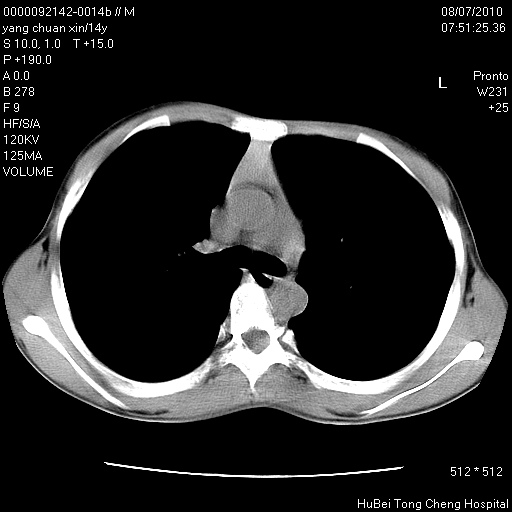

患者 女,36岁。右侧腰腿痛半月余。腰骶椎mr平扫偶然发现骶椎异常信号。

临床诊断:1)腰椎间盘突出症。2)骶椎肿瘤性病变?

骶椎ct平扫(层厚、层距均为5mm),图像如下: